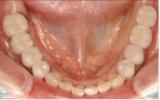

| 骨がなく今まではインプラント治療をあきらめていた患者さんも、インプラントに必要な骨を再生することによりインプラント治療が可能な時代になりました。 | ![]() |

【術前】 |

【術後】 |